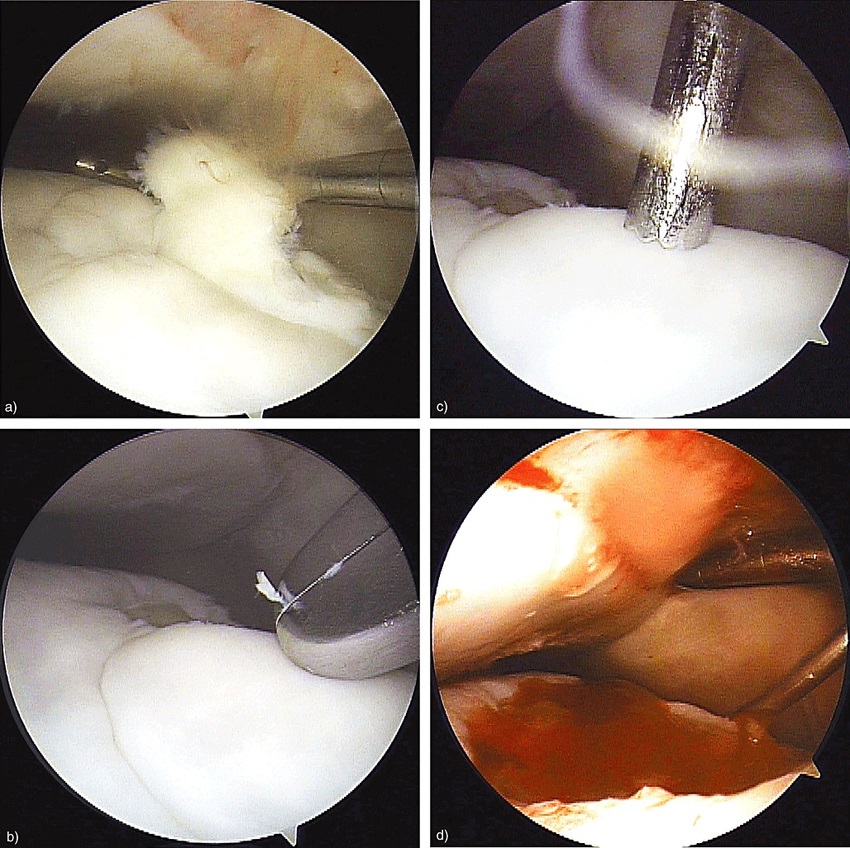

临床兽医可以通过临床症状作出初步诊断。确诊需要做X线片检查。例如上图中红圈内是一块很明显的游离于球节的骨软骨碎片。可以采用关节镜做进一步检查,以确定关节的损伤程度并通过微创手术去除软骨碎片,如下图。在国外,马主通常会在马匹三四岁的时候请兽医做一次全面的X线片检查评估它们的关节,一旦发现OCD,及早进行手术能最大程度减少其对关节的损伤,保住马儿未来的运动生涯。